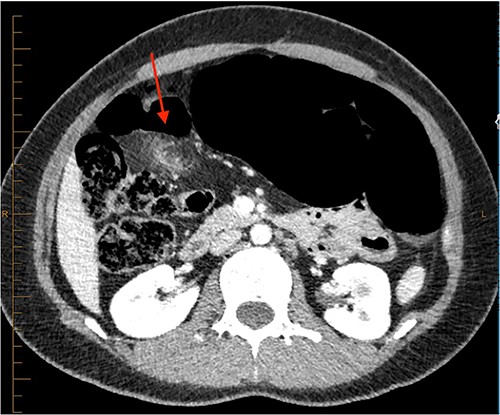

On review of imaging, we noted a CT scan from 2019 which showed swirling and stranding of omentum/mesenteric fat inferior to hepatic flexure (CC 1.8 cm, TV 2.6 cm), with suspicion of internal herniation of the omental/mesenteric fat leading to infarction (Figs 1 and 3). Management of this was unclear as this was at a private hospital in metropolitan Western Australia. A repeat CT scan during her current presentation revealed similar swirling of omentum/mesenteric fat, but with interval increase in size (CC 5.5 cm, TV 7.6 cm). There was associated small bowel dilatation and wall thickening and enhancement with no focal transition point (Figs 2 and 4).